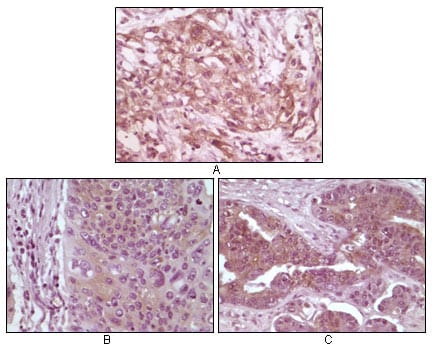

分类: 科研抗体货号: 20108别名: BRAF应用: IHC反应种属: Human

分类: 科研抗体货号: 20109别名: DYN2; DYNII; CMTDI1; CMTDIB; DI-CMTB; DNM2应用: IHC反应种属: Human

分类: 科研抗体货号: 20107别名: PR; NR3C3; PGR应用: IHC反应种属: Human